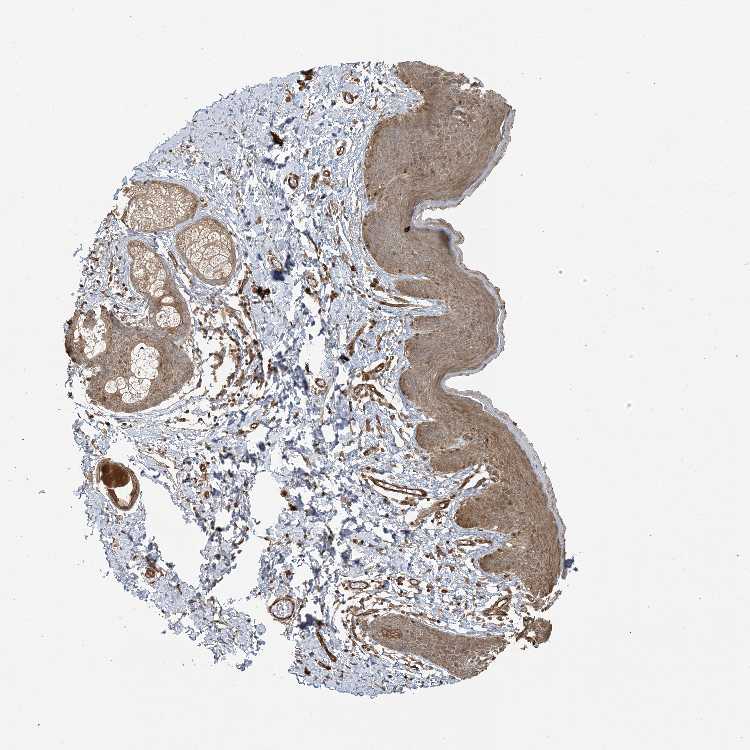

SKIN 1 - Antibody stainingi

Antibody staining in the annotated cell types in the current human tissue is reported as not detected, low, medium, or high, based on conventional immunohistochemistry profiling in selected tissues. This score is based on the combination of the staining intensity and fraction of stained cells.

Each image is clickable and will lead to virtual microscopy that enables deeper exploration of all samples and also displays staining intensity scores, fraction scores and subcellular localization as well as patient and tissue information for each sample.

Antibody HPA035027Antibody HPA035028

Langerhans Not detectedMedium

Fibroblasts Not detectedMedium

Keratinocytes Not detectedMedium

Melanocytes Not detectedMedium